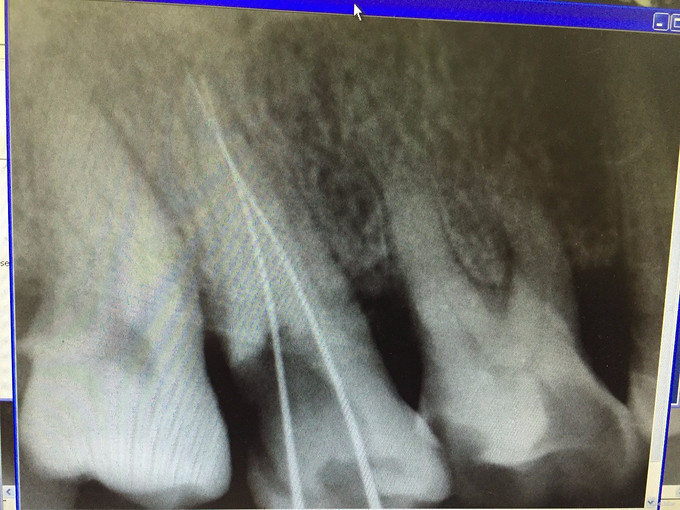

检查: #17#18之间出现大量食物残渣,去除后见大量腐质及牙色充填体,去腐后见穿髓孔,#17叩(+-),松(-),冷热测不适,电测有活力,扪诊无不适,#18叩(-),松(-),冷热侧正常,电测有活力,牙龈稍红肿。 X线示: #17高密度充填体,根尖未见明显阴影。

诊断:#17慢性牙髓炎 处理: #17碧兰麻下开髓、揭全顶,寻找根管口,拔髓,次氯酸钠和双氧水交替超声冲洗,测量工作长度,根管预备,封Ca(OH)糊剂2两周,ZOE暂封。两周后复诊检查,患牙无叩痛,患者无不适,暂封存。去暂封,次氯酸钠和双氧水交替超声冲洗,再次测量工作长度,干燥,热牙胶充填。树脂充填治疗。